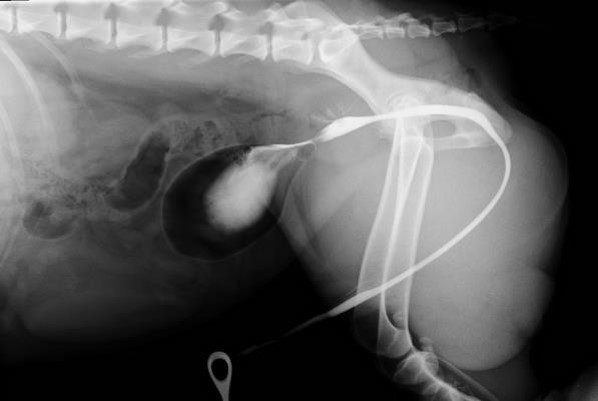

What has created this image?

What is seen?

What is the likely diagnosis?

Positive cystogram

Normal cranial bladder

Caudally – bisected structure

Size over 70% of pelvic inlet – prostate

This is classic for BPH – benign prostatic hyperplasia (smooth)

What is this?

Smooth symmetrical enlargement consistent with BPH

Less marked enlargement with irregular contrast leakage suggestive of neoplasia